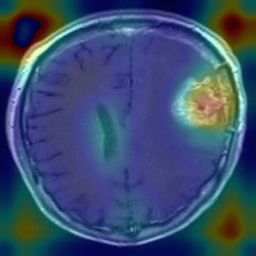

Figure 1: Heatmap Comparison of Unhealthy Images. Different columns show unhealthy MRI images of different positions, sizes, and textures. The first row is the raw image. The second row is the heatmap predicted with PatchCore. The third raw is the heatmap predicted with the proposed method.